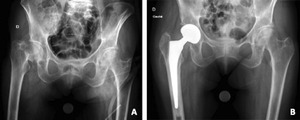

Worldwide, HA remains the most frequently performed procedure for displaced FNFs, particularly in patients over 70 years of age or those with significant medical comorbidities.11,19 (Figure 1) Although technically less demanding and faster to perform than THA, HA offers a lower risk of dislocation and reliably restores mobility in frail, low-demand patients. However, these short-term advantages are counterbalanced by long-term risks, including acetabular erosion, inferior functional outcomes compared with THA, and, in some cases, the subsequent need for conversion to THA.53

THA has increasingly been adopted for the management of displaced FNFs in selected patients, particularly those who are younger, higher functioning, and medically fit. Evidence consistently shows that THA offers superior functional outcomes compared to HA, although at the cost of higher complication rates. (Figure 2)